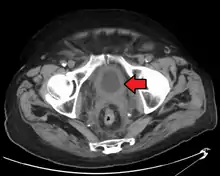

Bladder wall thickening due to cancer